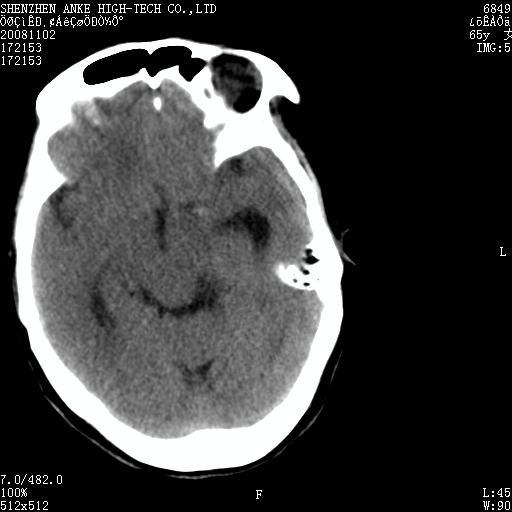

患者,女性,65岁,突发右侧肢体无力伴头痛,恶心、呕吐3小时.

1 左侧顶区圆形病灶,内可见钙化,考虑脑膜瘤,建议增强。2 左侧侧脑室病变,考虑神经上皮囊肿。

1)左侧顶区脑膜瘤可能性大;建议必要时行进一步检查。2)左侧脑室积水。

左顶部脑膜瘤,左侧侧脑室蛛网膜囊肿,建议增强.

左侧脑外占位(脑膜瘤)压迫脑实质、脑室侧室孔所致积水。支持!